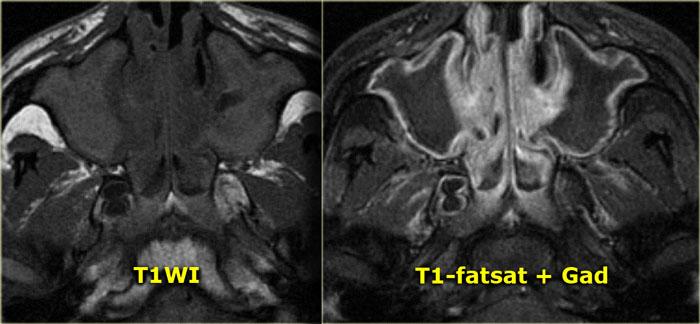

Bên trái là ví dụ về bệnh lý xoang mũi do nhiễm trùng.

Trên ảnh trước tiêm thuốc tương phản từ, thấy nội dung tín hiệu tương đối cao trong các xoang hàm do vật chất giàu protein.

Sau khi tiêm thuốc tương phản từ đường tĩnh mạch, chỉ có hình ảnh ngấm thuốc của niêm mạc xung quanh và không có ngấm thuốc dạng đặc.